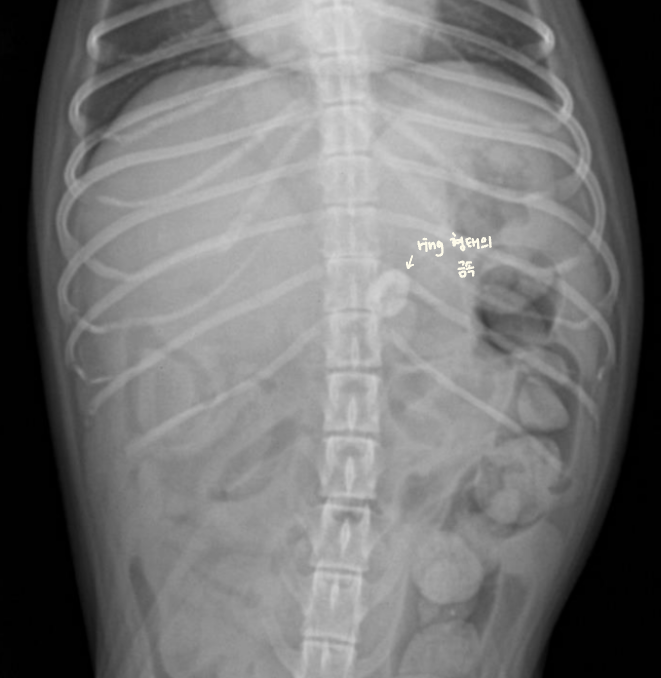

| hairball, ์ฒ, ์ค (๊ณ ์์ด) - ์กฐ์์ ๋ฐฐ์ถ์ด ๋งค์ฐ ๋๋ฆผ (1์๊ฐ์ด๋ฉด ๋๊ฐ์ผ ํ๋๋ฐ, ๋ง 8์๊ฐ..) โ์ ๋จน๊ณ ์ ๋ ธ๋๋ฐ ๊ฐํ์ ์ผ๋ก ๊ตฌํ ํ๋ค โ โ ํค์ด๋ณผ ์์ฌ |

![]() |